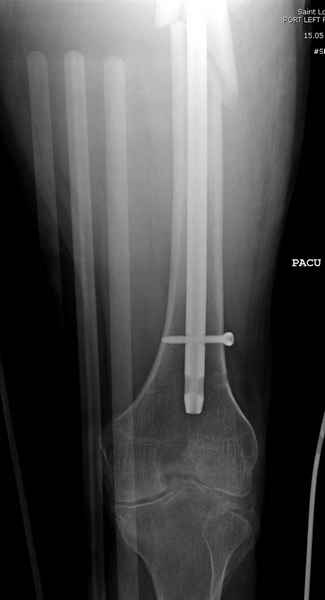

Учитывая, что случай ургентный, больной поступил вечером, не стали делать вытяжение и срочно провели операцию по фиксации перелома бедра антеградным штифтом Versa Nail от DePuy.

Для профилактики дальнейшего раскола в шейке предварительно во время проксимального рассверливания спереди и сзади провели временные спицы, которые в дальнейшем были заменены на шурупы (miss nail method)

Кровотечение удалось контролировать, и больной через пару дней выписан на амбулаторное лечение.